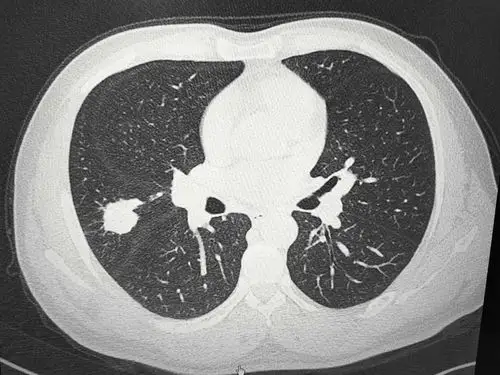

性肺结核-/上中下 涂(-)进展期,初治 写美篇 比较典型的肺结核病灶